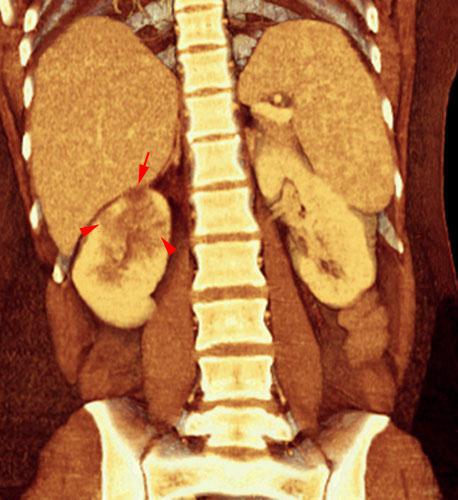

Pielonefritis aguda 1